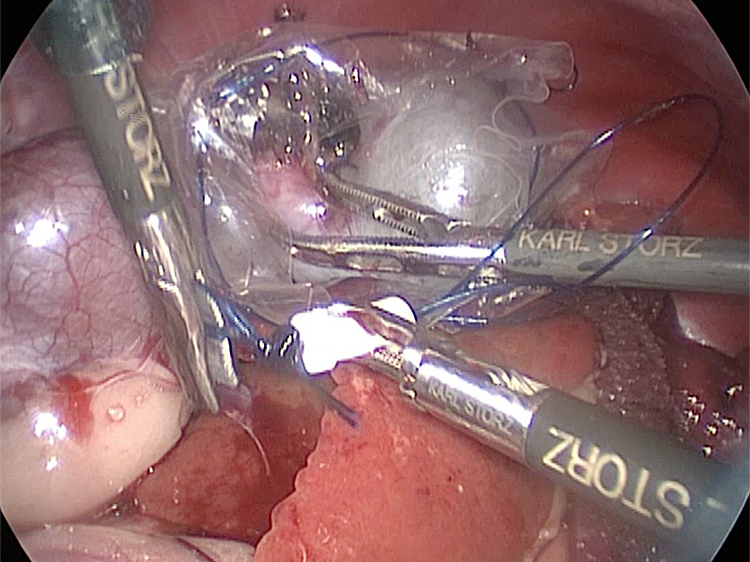

お腹にトロッカーを4本挿入し、そこから鉗子とカメラを入れて胆嚢を肝臓から剥がしていきます。 カメラで拡大しながら見ることができるので開腹手術よりも視野が確保できます。

癒着(矢印)がひどく胆嚢を確認することができませんでした。 このように癒着しているときはギリギリで剥がすとひどく出血をおこすことがあるので無理にはがそうとしないで、脂肪の血管に注意しながら脂肪ごと剥がしていきます。

胆嚢の頸部に糸を通し動脈を確保しています。